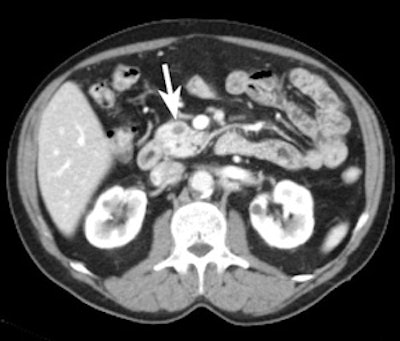

The oncological issue of infiltration affects pancreatic tumors in particular. When assessing preoperative tumor respectability, the most frequent and important question for the surgeon is the relationship between the tumor and the adjacent vessel in order to understand whether the tumor can be separated from it, Manfredi explained. When fat can be detected between the vessel and the tumor, the tumor can be resected, but when the vessel is totally encased by the tumor, it can't. These two extreme examples represent the relatively easy cases, but in the majority of cases in which there is contact between the vessel and the tumor, it is difficult to preoperatively predict whether the surgeon will be able to pass his or her finger between the two, enabling resection, he noted.

"From the pathological point of view, the nature of the tissue responsible for the contact is the main determinant, with direct tumor contact most likely rendering it nonresectable. If contact is made through inflammatory/desmoplastic reaction, it is most likely to be resectable," said Manfredi, emphasizing that Zamboni's input is needed for more difficult cases.